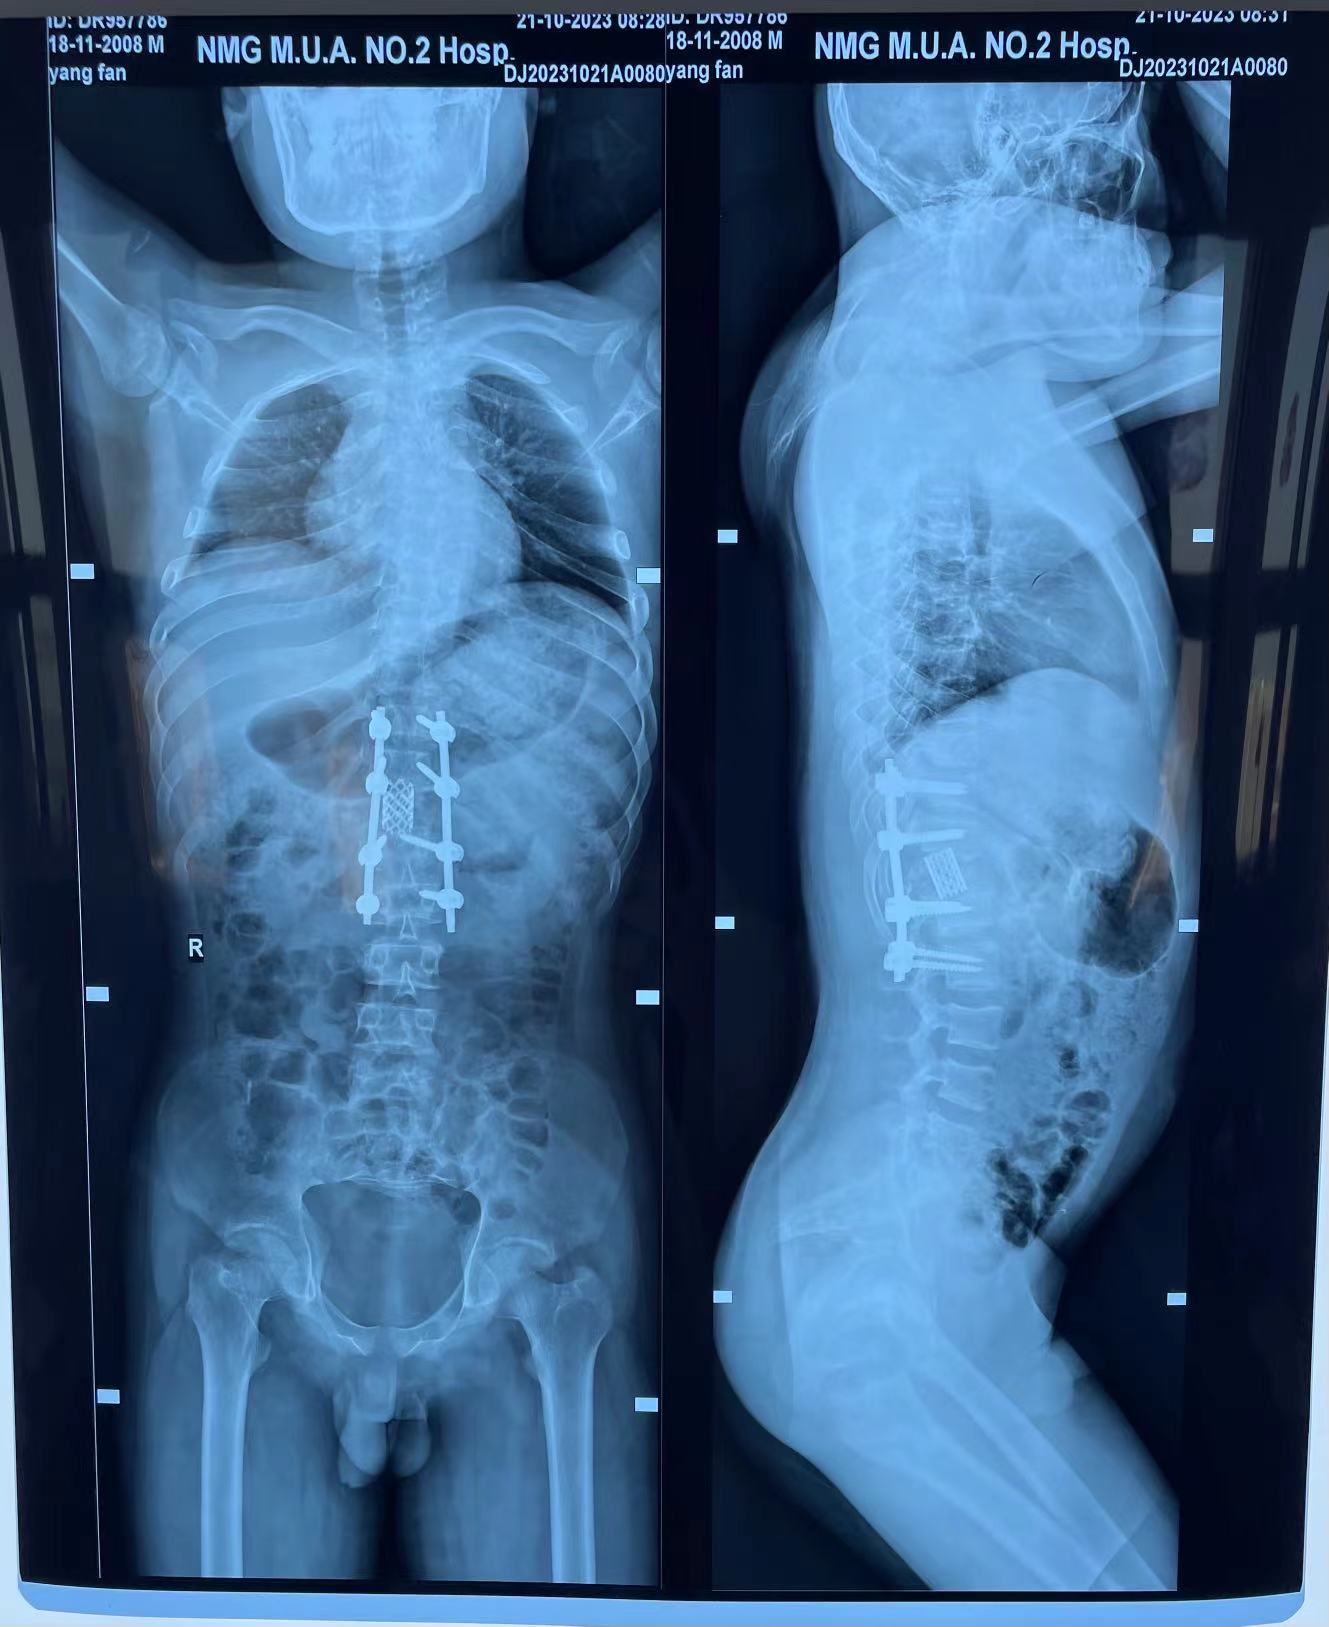

脊柱外科中心D区辛大奇、王东海、孙洪岩医疗团队完善患者术前检查后,明确诊断为胸12半椎体侧后凸畸形,经过积极与胡侦明教授沟通、讨论后,共同为患者制定手术方案,为患者施行先天性脊柱侧弯、半椎体侧后凸畸形截骨矫形+植骨融合内固定术。

胡侦明教授不远万里,亲临91直播 参加会诊并给予手术指导,最终在胡教授和91直播 医护团队的通力协作下,手术顺利完成,患者术后继续接受恢复治疗,状态良好,患者双下肢功能明显改善。近日,患者已顺利康复出院。